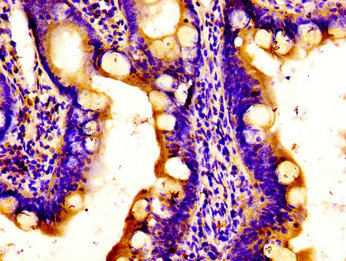

Immunohistochemistry of paraffin-embedded human small intestine tissue using CSB-PA846585LA01HU at dilution of 1:100